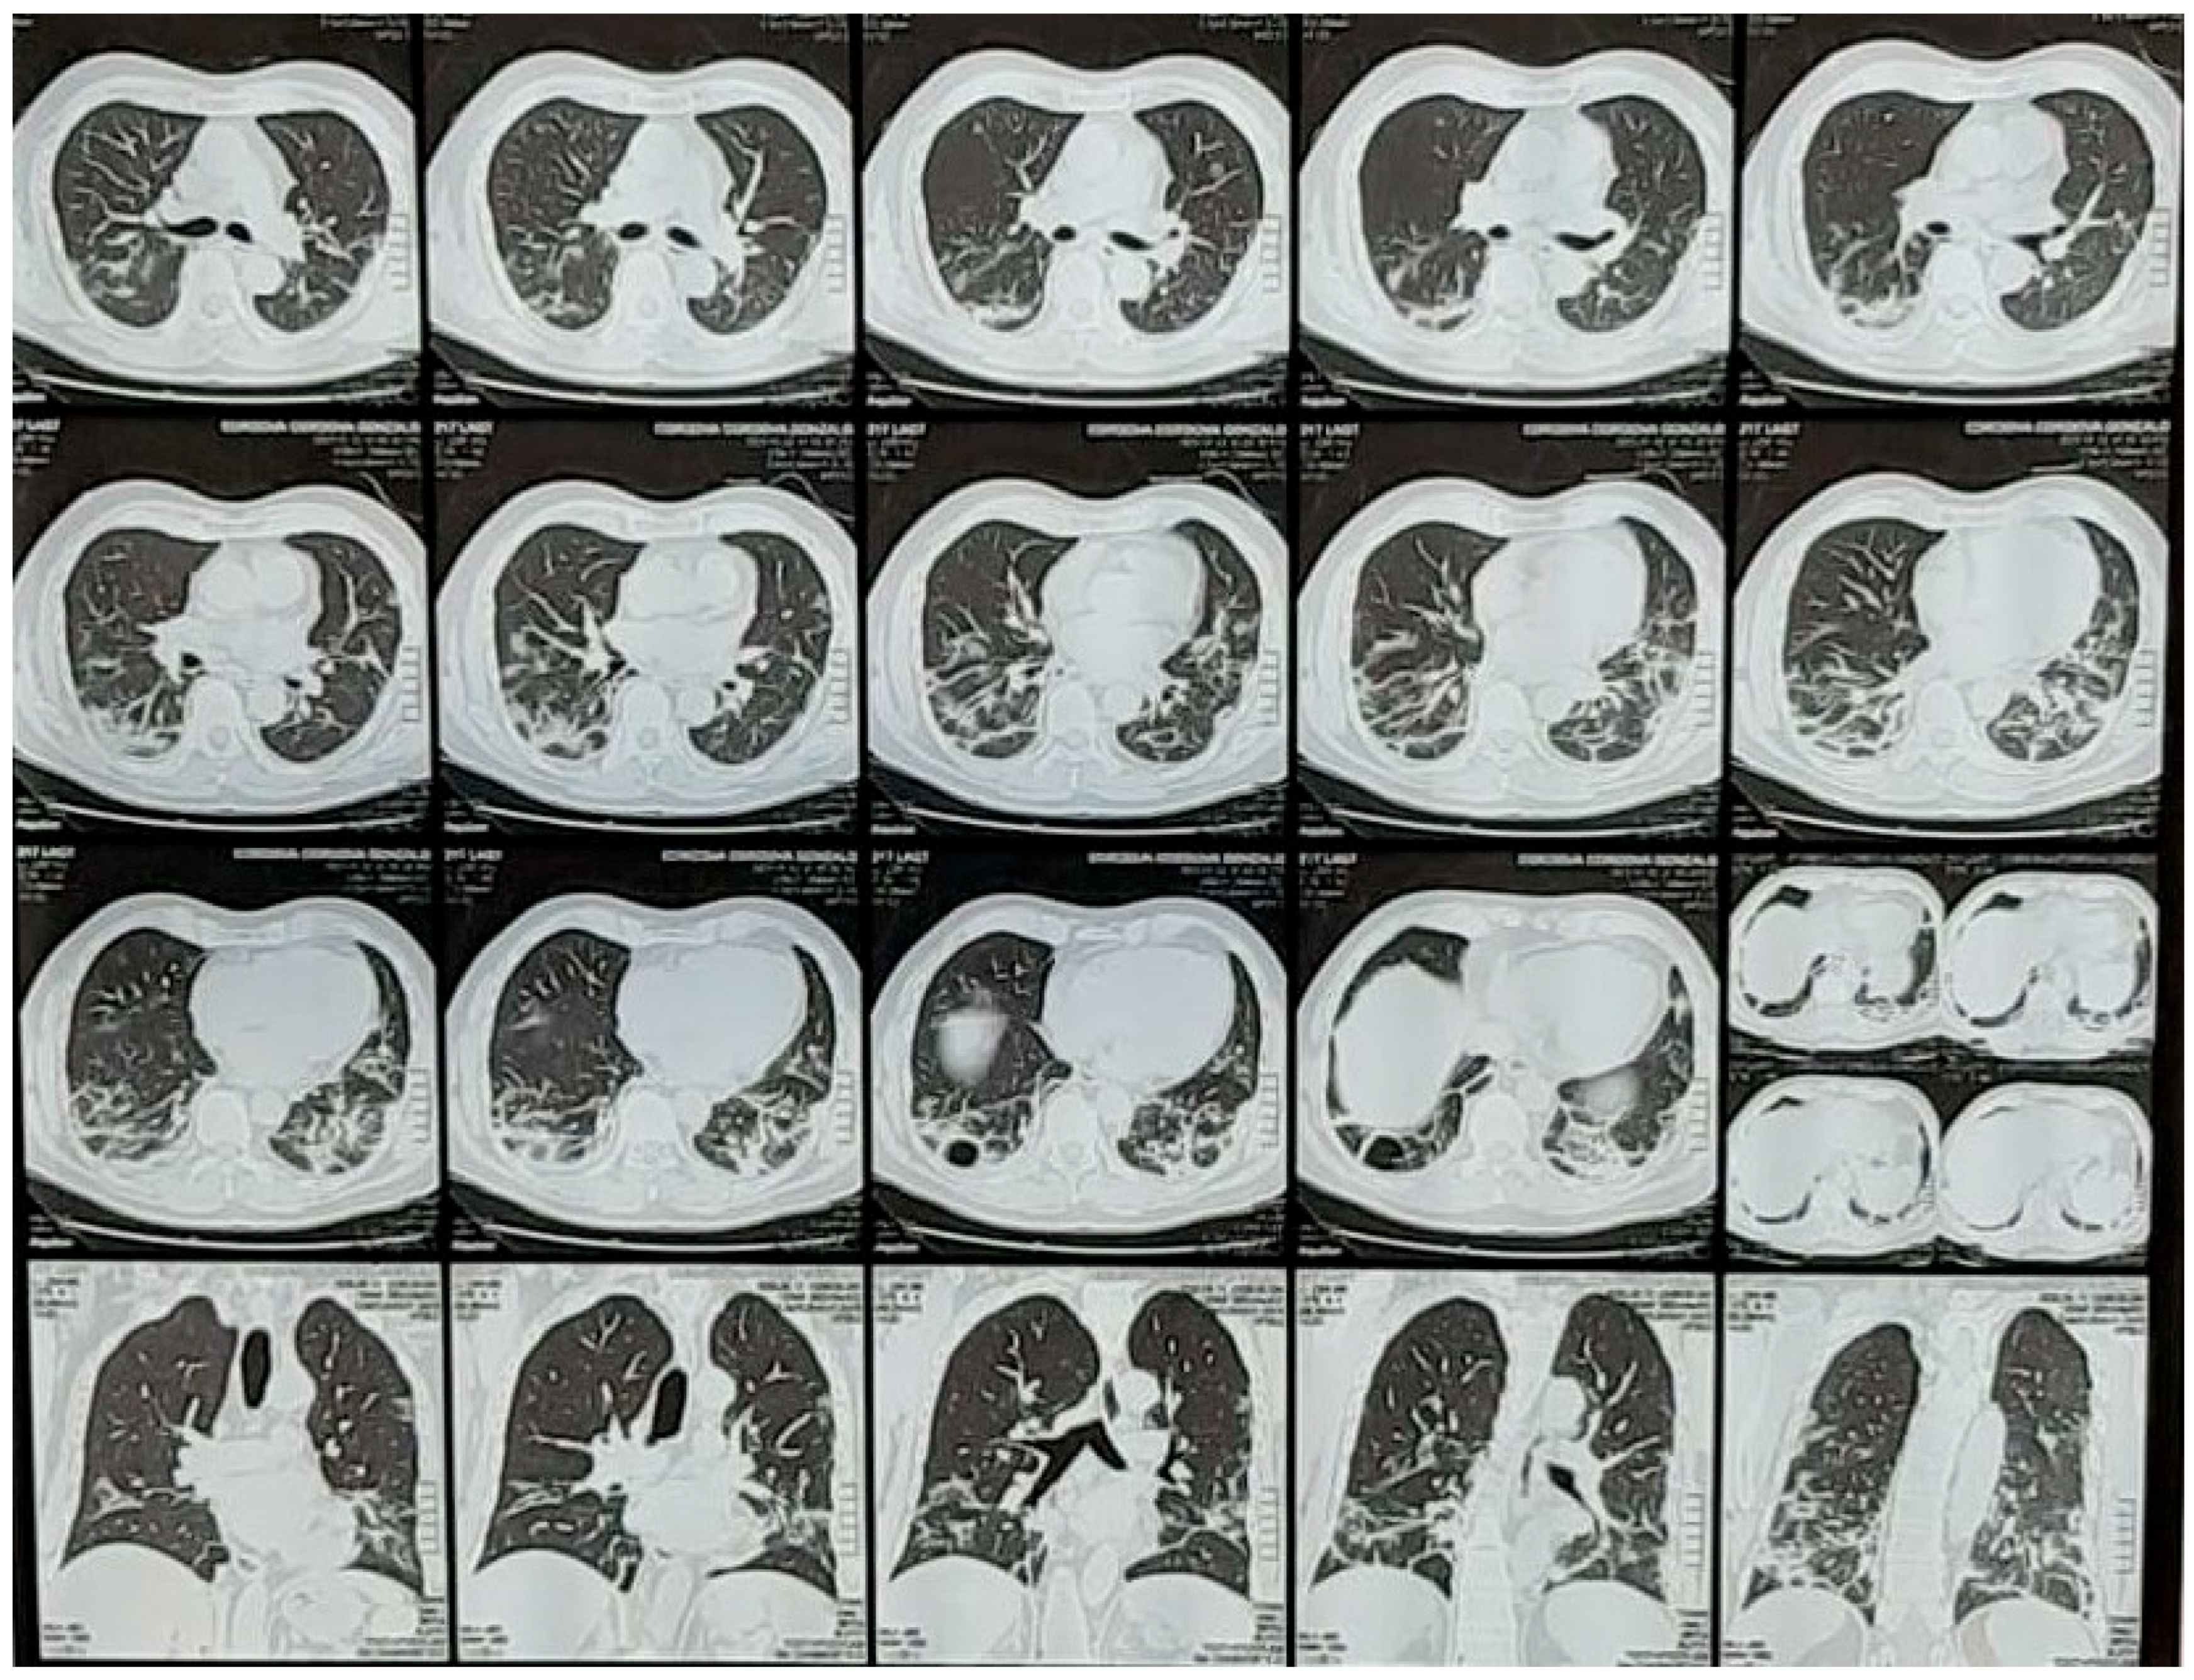

In 2019, the COVID-19 CAT scan compromise presented a distinct pathology (Figure 1). Some authors noted that it was different but did not fully understand it and suggested autopsies be performed [7]. Several autopsy studies of COVID-19 show fibrotic, bullae-filled, necrotic lung tissue, clearly distinct from SARS-CoV-1, which is more hemorrhagic (personal communication by Paolo Pelosi). Others reported diffuse alveolar damage (DAD) [14], chronic lung inflammation, and edema in the bronchial mucosa, with some finding thromboembolic events [15,16].

Figure 1.

CT scan of a typical patient with COVID-19 lung disease. Courtesy of Centro de Estudios Tomográficos (CET) La Paz, Bolivia. Pneumolysis can be so severe that even bullae can be formed (3rd row, middle frame).

COVID-19 is a fast-track production of emphysema-type lesions, as it destroys alveoli without time for remodeling and adaptation. It creates bullae (Figure 1) and small cavities similar to those seen in TB. These bullae were also present in previous biopsies [31]. Mycobacterium tuberculosis proliferates inside alveolar macrophages and eventually kills the cells [32]. The tuberculosis attack is intracellular, making treatment difficult and requiring long-term therapy for up to a year. The infected macrophages produce cytokines and chemokines that attract other phagocytic cells, including monocytes, other alveolar macrophages, and neutrophils, which eventually form a nodular granulomatous structure called the tubercle [33]. However, this takes quite a bit of time. In COVID-19, there is no time, as the intracellular coronavirus bio-attack is fast. The same phagocytic cells are, however, present in COVID-19, as described below. Adaptation to survival within the disease takes time. The high-altitude adaptation formula shows a typical hematopoietic time frame in response to ascent to a fixed high altitude [34], which requires 40 days for an optimal increase in hematocrit at 3600 m (12,000 ft.).